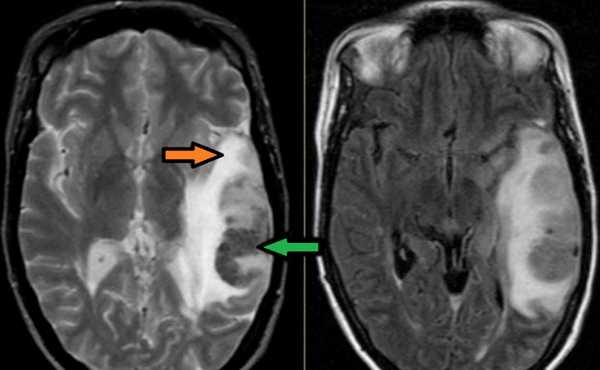

МР-ангиография при нарушении венозного кровоснабжения височных долей

МРТ сосудов головного мозга: артериография, венография